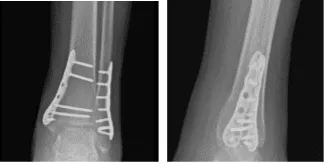

Para entonces, se aconsejó al paciente que realizara la Práctica R.I.C.E (Reposo, Hielo, Compresión y Elevación). Se revisó y monitorizó la radiografía del tobillo izquierdo durante 32 semanas postoperatoria, mostrando fracturas quirúrgicamente tratadas en el peroné distal y la maléola medial.

Radiografía del tobillo izquierdo completada 3 o más visitas 8 semanas después de la operación

Radiografía del tobillo izquierdo completada 3 o más visitas a las 16 semanas postoperatorias

Radiografía del tobillo izquierdo completada 3 o más visitas 8 meses después de la operación